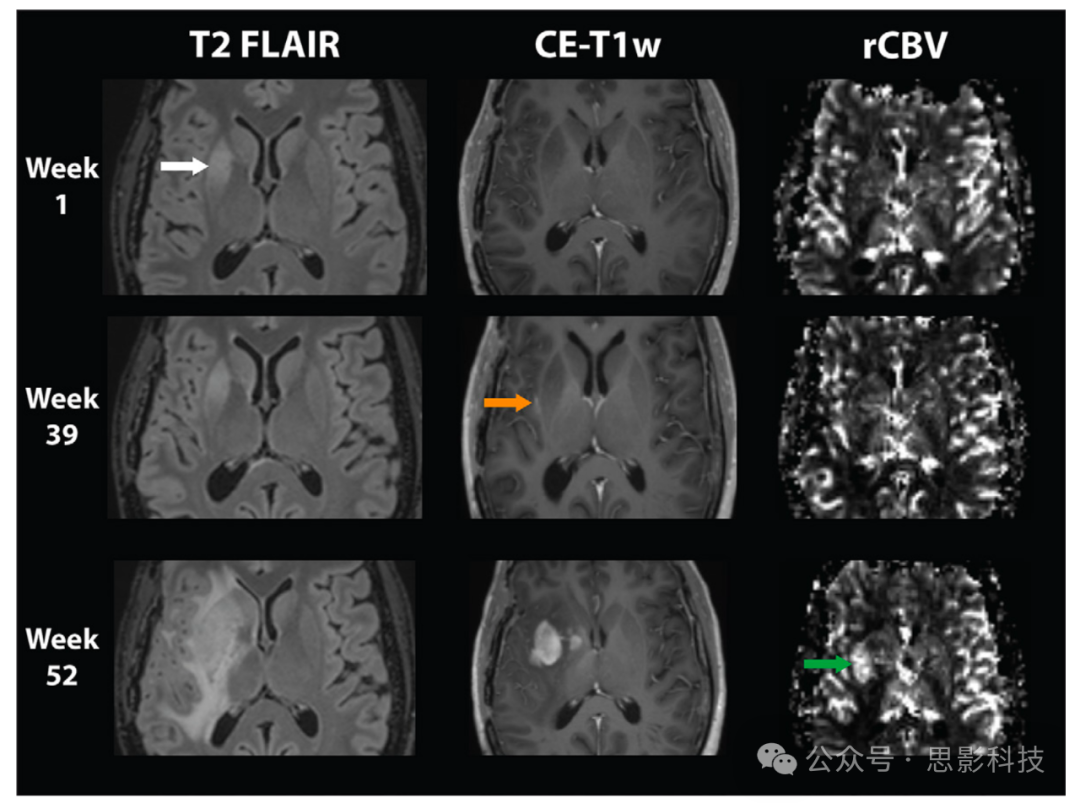

在原发性脑肿瘤成像中,不含对比增强(CE)序列的MRI方案通常被认为不足以满足诊断目的(1)。通过使用钆对比剂(GBCAs),T1加权CE图像有助于勾画病变边界、鉴别实体并评估疗效。最常用的脑灌注技术——动态磁敏感对比(DSC)MRI,也依赖于GBCA注射(图1)。

图1:T2液体衰减反转恢复(FLAIR)图像、对比增强T1加权(CE-T1w)图像以及动态磁敏感对比灌注相对脑血容量(rCBV)图是原发性脑肿瘤评估的支柱。该示例说明了这三个序列在一例异柠檬酸脱氢酶野生型胶质母细胞瘤患者一线治疗后随访中的独立价值和表现,患者于治疗结束后3个月(第1周)进行随访。右侧基底节区出现新的高信号(白色箭头,第1周),因此在39周后观察到微弱的对比增强(橙色箭头,第39周),52周后该区脑血流量上升(绿色箭头)。请注意,不同序列受累的脑区不同。